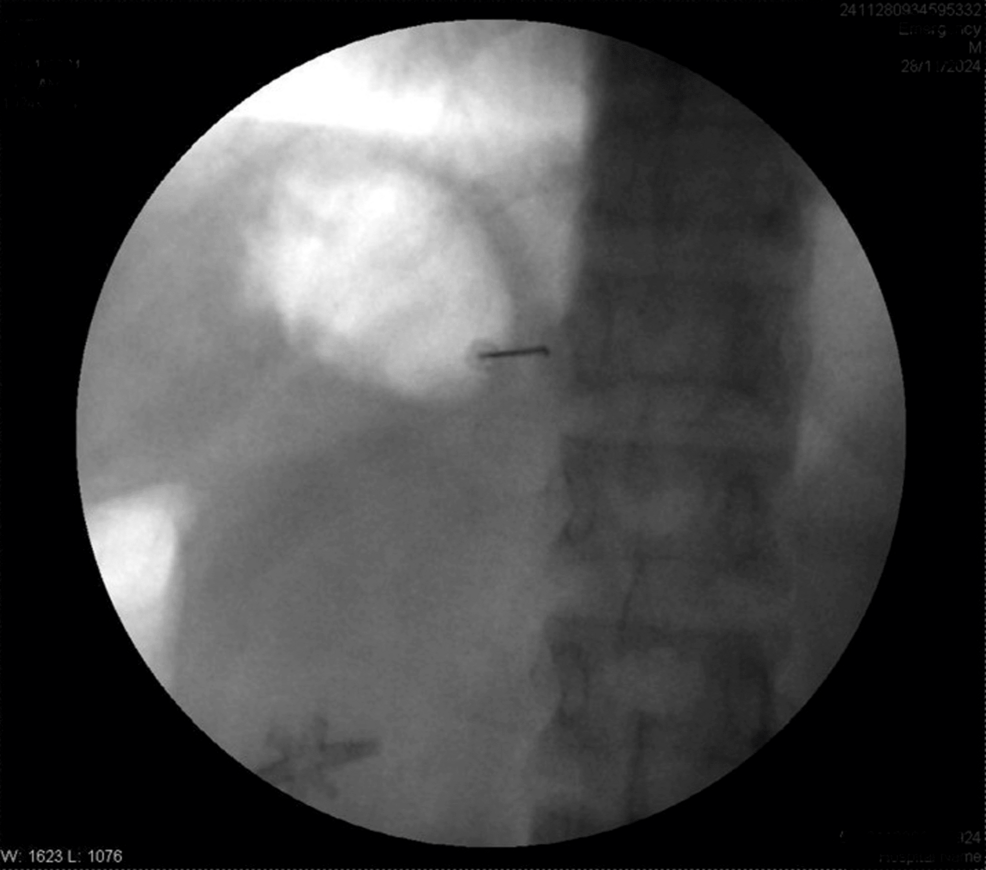

The patient was positioned prone. After painting and draping, the transverse process of T8 was located on the right side with the help of a C-arm. A Quincke needle (22 G) was inserted under fluoroscopic guidance to reach the transverse process of T8. The needle tip was advanced caudally along the transverse process until a loss of resistance was felt. The needle’s position was confirmed via fluoroscopy by injecting iohexol 300 radiocontrast dye, with images obtained in both anteroposterior and lateral views (Figures 1–4).

Four milliliters of levobupivacaine 0.5% were administered. Similar steps were performed for the T10 and T12 vertebrae. Sensory levels were assessed using hot and cold glass test tubes along the mid-axillary line. Motor blockade was evaluated using Snider’s match-blowing test, where the patient was asked to blow out a match held 15 cm from the mouth. Vitals after five minutes were HR of 90/min, BP of 100/68 mmHg, SpO2 of 98%, and RR of 14/min.